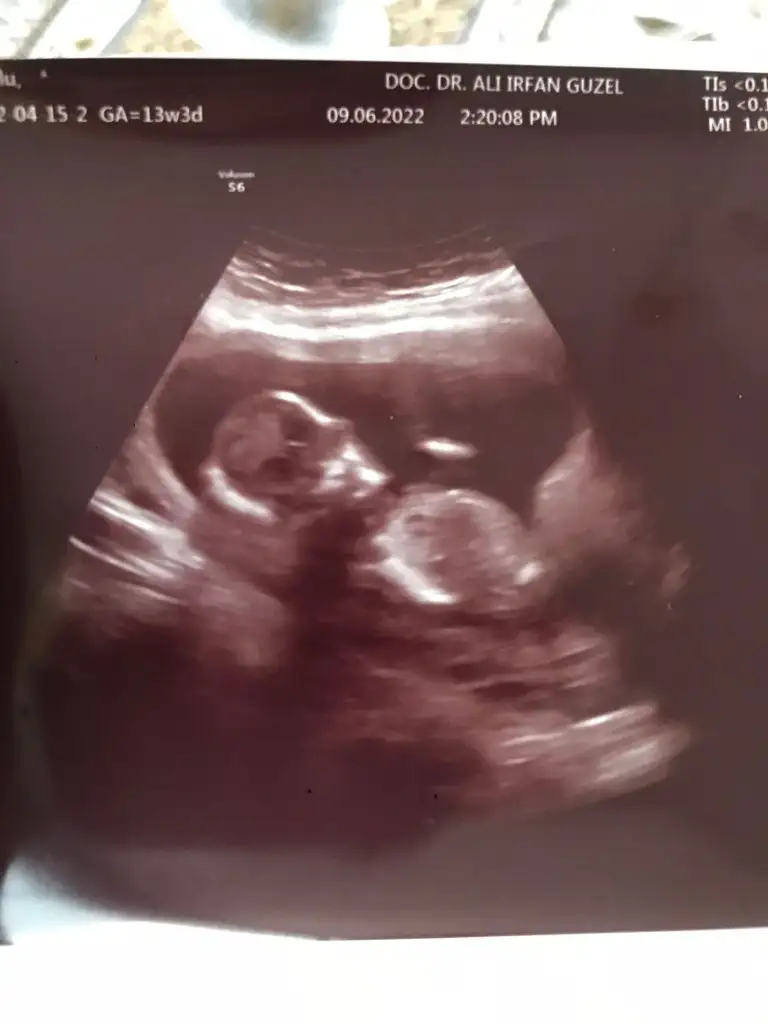

Merhabalar, rica etsem benim yeğenim için de tahminde bulunur musunuzz ☺️ 13+3 karından usg

Eklentiler